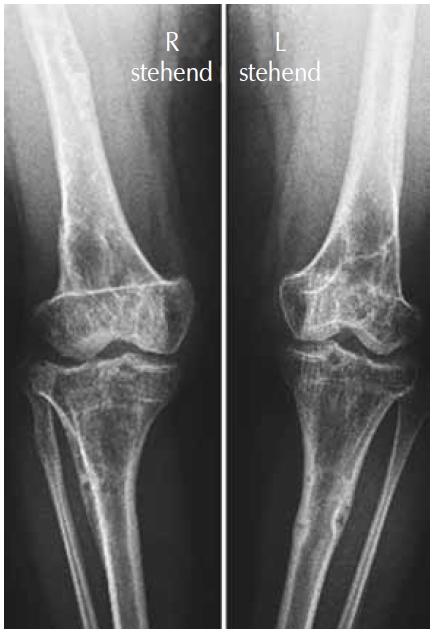

AP knees and lower femora radiographs showed a combination of osteoporosis, osteolytic islands along the cortices, and fibrocartilaginous changes (Fig. 3).

Fig. 3. AP knees and lower femora radiographs showed a combination of osteoporosis, osteolytic islands along the cortices, and fibrocartilaginous changes